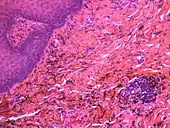

| Amalgam tattoo in upper labial sulcus in an edentulous individual, left behind after teeth have been lost/extracted | |

If necessary, the diagnosis can be confirmed histologically by excisional biopsy, which excludes nevi and melanomas.[3]: 138 If a biopsy is taken, the histopathologic appearance is:[1]

- Pigmented fragments of metal within connective tissue

- Staining of reticulin fibers with silver salts

- A scattered arrangement of large, dark, solid fragments or a fine, black or dark brown granules

- Large particles may be surrounded by chronically inflamed fibrous tissue

- Smaller particles surrounded by more significant inflammation, which may be granulomatous or a mixture of lymphocytes and plasma cells